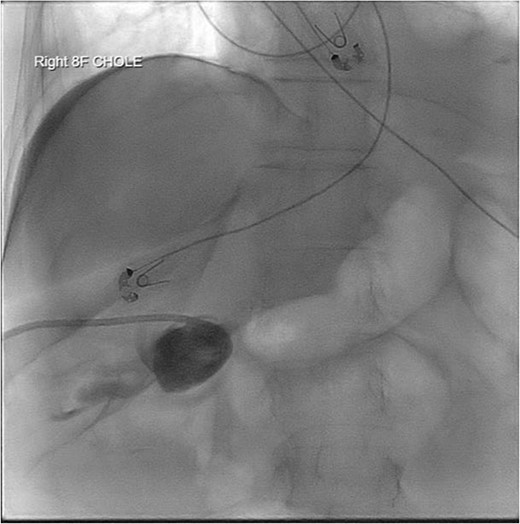

Repeat imaging was performed and revealed peri-hepatic ascites, significant anasarca and bilateral pleural effusions (Fig. 3) while the PCT remained in good position (Fig. 4). Bilateral chest tube placement and drainage of the pleural effusions revealed chylothorax and malignant cells. Cultures of both PCT output at the time of insertion and pleural fluid cultures grew no organisms.

Computed tomography (CT) chest demonstrating bilateral pleural effusions.